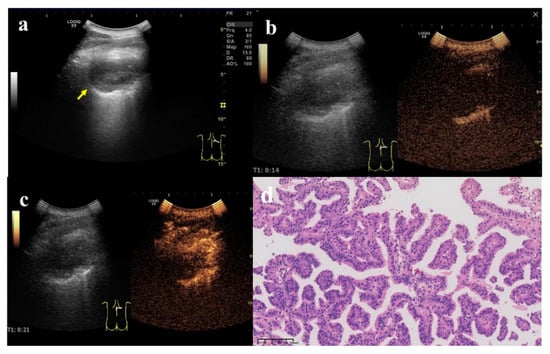

Figure 5. A 58-year-old male with a lesion occupying the deep space in the lower corner of the right shoulder armor. (a) Two-dimensional ultrasound showed a hypoechoic nodule, size 5.5 × 4.5 cm (arrow). At least one angle (between lesion border and thoracic wall) was obtuse. (b) Contrast-enhanced ultrasound showed that the enhancement time of lung tissue was 10 s and that of nodule was 14 s. (c) The enhancement began from the periphery to the center. The enhancement reached the peak in 30 s, and the enhancement degree was obviously uneven. (d) Pathologic evaluations revealed lung adenocarcinoma, mainly solid and acinar (×200).